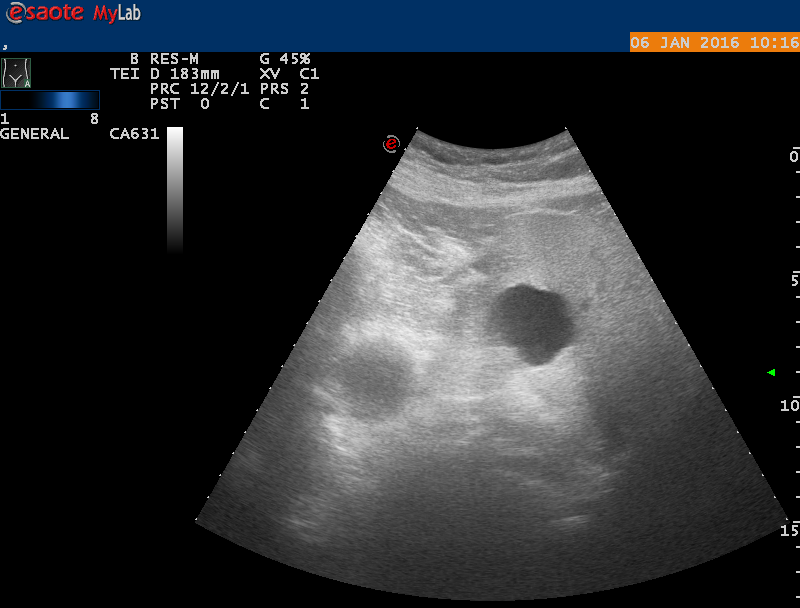

женщина 65лет жалобы на боли в эпигастрии помогите разобраться что это

Похоже на простую кисту.

Киста,похоже.Жаль,что нет скана с поджелудочной,желчным.может там причина болей?